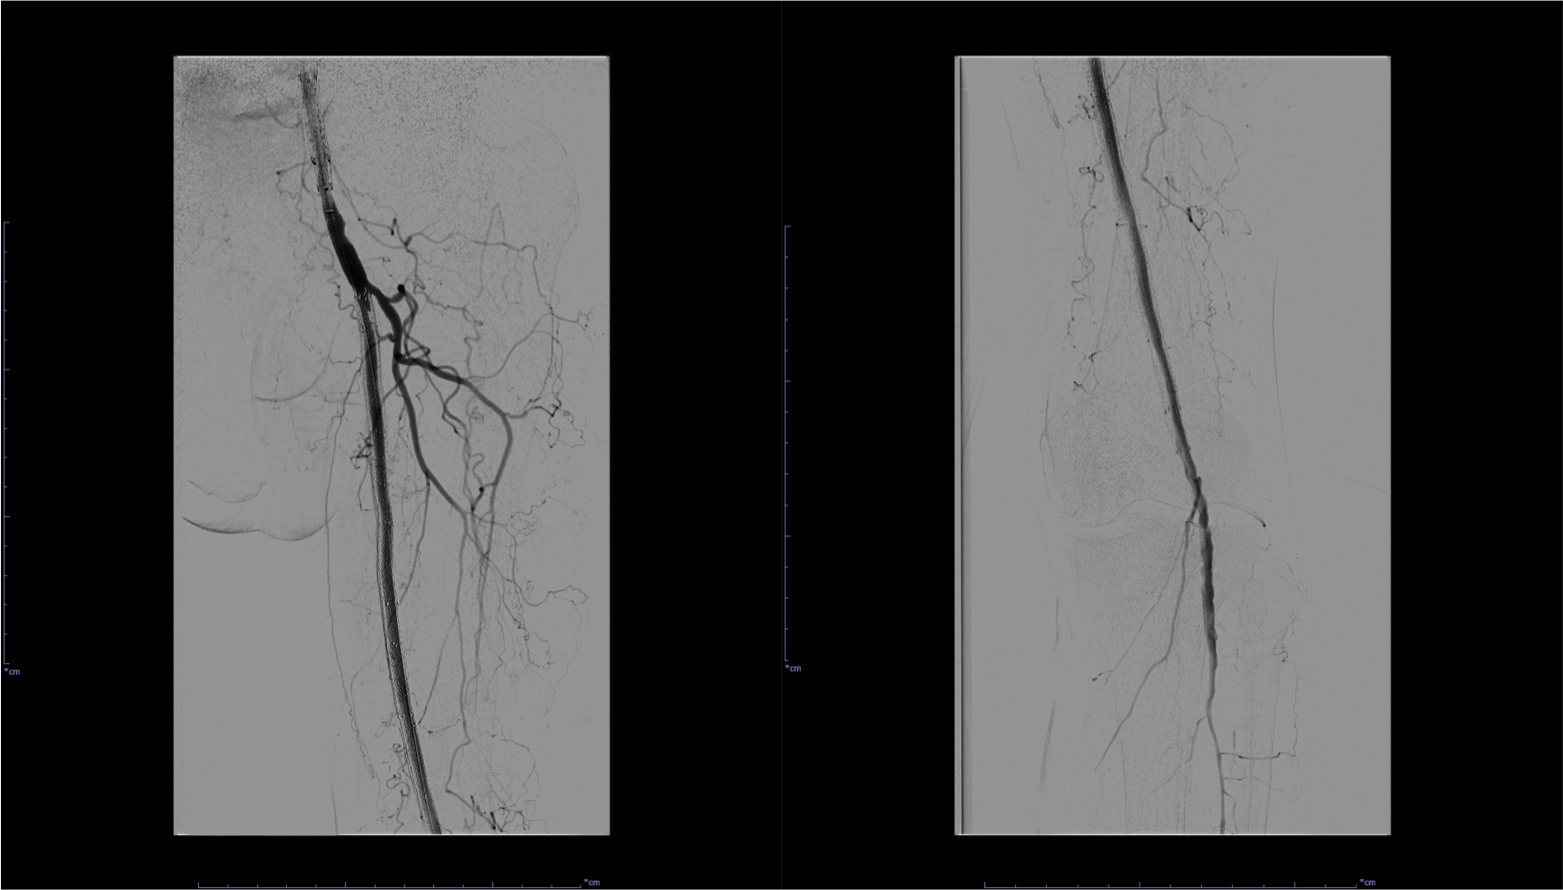

図4.左SFA~Pop. A血管造影(治療前)

左SFA~Pop. Aステント内およびステント遠位部の閉塞が認められる